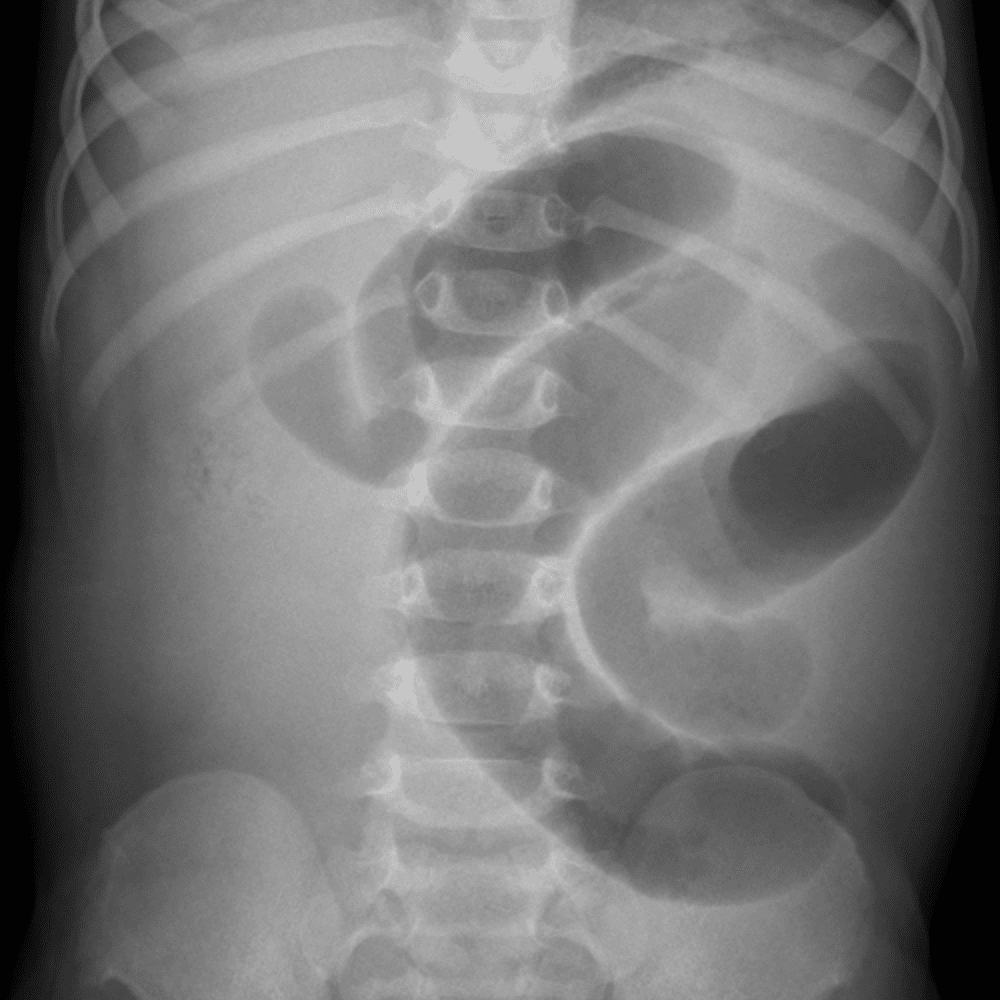

Peds Abdomen

Practice

Simulates call by including subtle or difficult cases and some normals.

30 cases